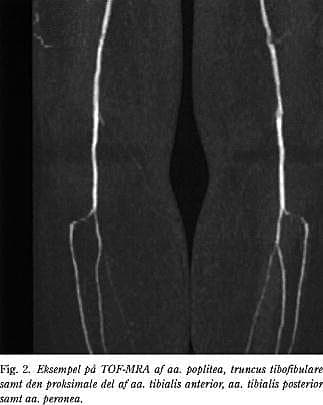

Den ikke-kontrastforstærkede MRA-teknik er baseret på signalforskellen imellem protoner i bevægelse i karret og stationære protoner i det omgivende væv. Den foretrukne MRA-teknik er den såkaldte time-of-flight-teknik (TOF-MRA) (Fig. 2). På grund af tidsforbruget og risikoen for artefakter har metoden dog aldrig vundet større udbredelse forud for arterielle rekonstruktioner, udtagen i enkelte karkirurgiske centre (2, 5). Artefakter ses specielt i stærkt kurvede arterier, fx i iliacasegmentet, hvor artefakterne vil overdrive stenosegraden og -længden. Trifasisk flow, der er et normalt fænomen i større arterier, kan ligeledes medføre artefakter, ligesom respirationsbevægelser og tarmperistaltik. En fuldstæn- dig TOF-MRA-undersøgelse fra aorta til fod tager 1-2 timer (2).